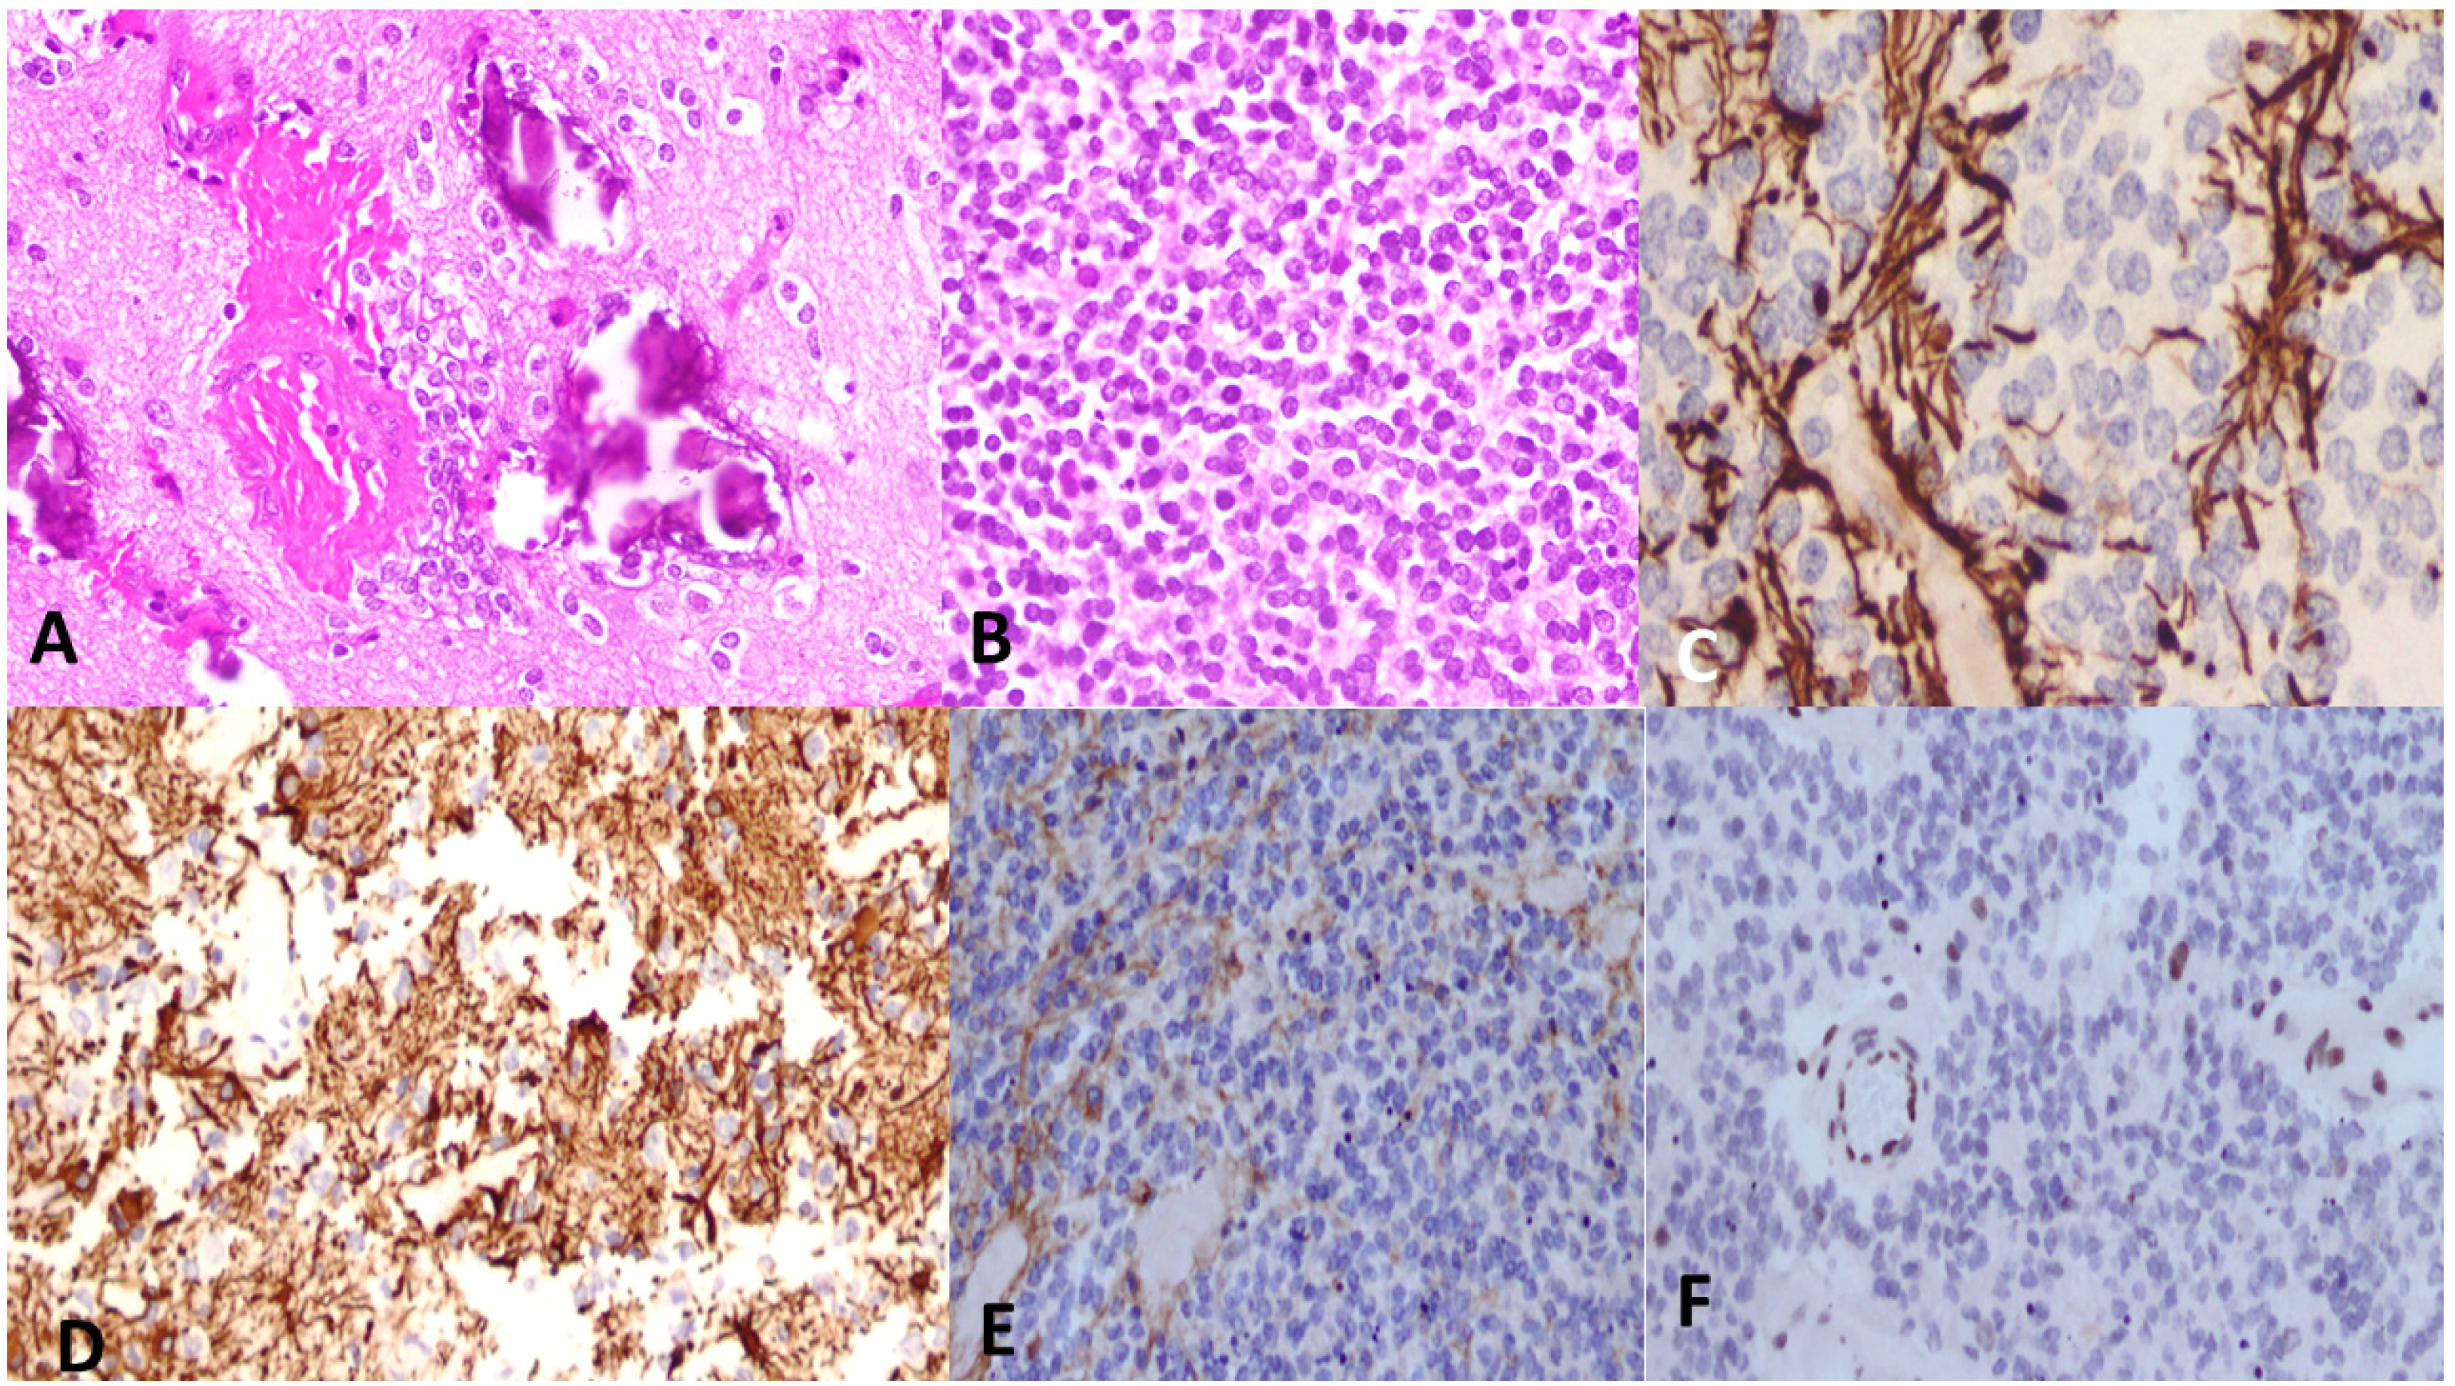

6. Histological Features